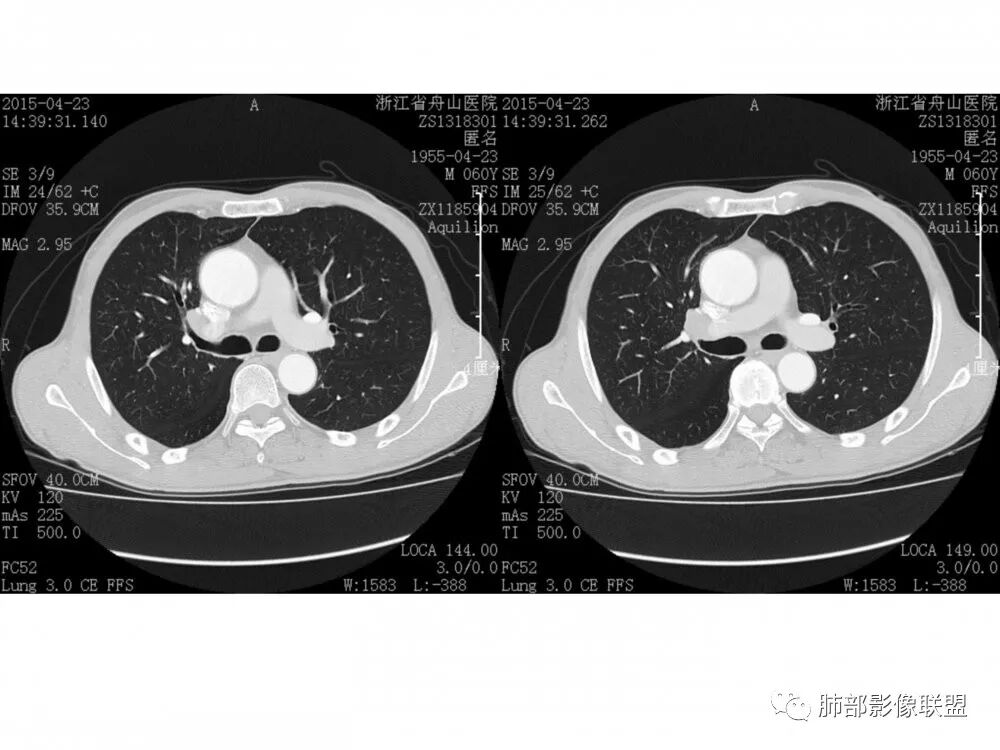

流心明智

老年男性,右肺下叶支气管开口新生物,基底干及中间支气管受累狭窄,支气管管壁破坏明显,强化低,不均匀,肺门、7组、4R淋巴结肿大,考虑恶性支气管腔内肿瘤,小、鳞可能大,需与类癌、粘表等鉴别。

老年男性,右肺下叶支气管腔内可见软组织密度影,向腔内突入,支气管壁破坏,向外突出,管腔明显狭窄,增强后轻度强化,伴纵膈及肺门多发肿大淋巴结,首先考虑恶性肿瘤,小细胞肺癌可能大,建议支气管镜检查

右中间、右下叶背段支气管管腔内见突向管内的管状软组织影,相邻支气管壁有侵犯,增强有强化,纵隔2R 、4R、10R组淋巴结肿大,增强有强化,未见ct值,常规考虑恶性肿瘤,小细胞癌并同侧纵隔淋巴结转移,鳞癌、类癌街排,建议支气管镜检查。

右肺下叶支气管开口新生物,轴位管腔及纵向基底干大部分受累狭窄,支气管管壁破坏并突破形成腔外肿块,血管累及变细,肉眼观轻度强化,右肺门、纵膈淋巴结肿大,恶性没问题,阻塞性炎症不明显,类癌强化明显不支持,老年男性,首先考虑小细胞癌,鉴别不典型鳞癌和腺癌。